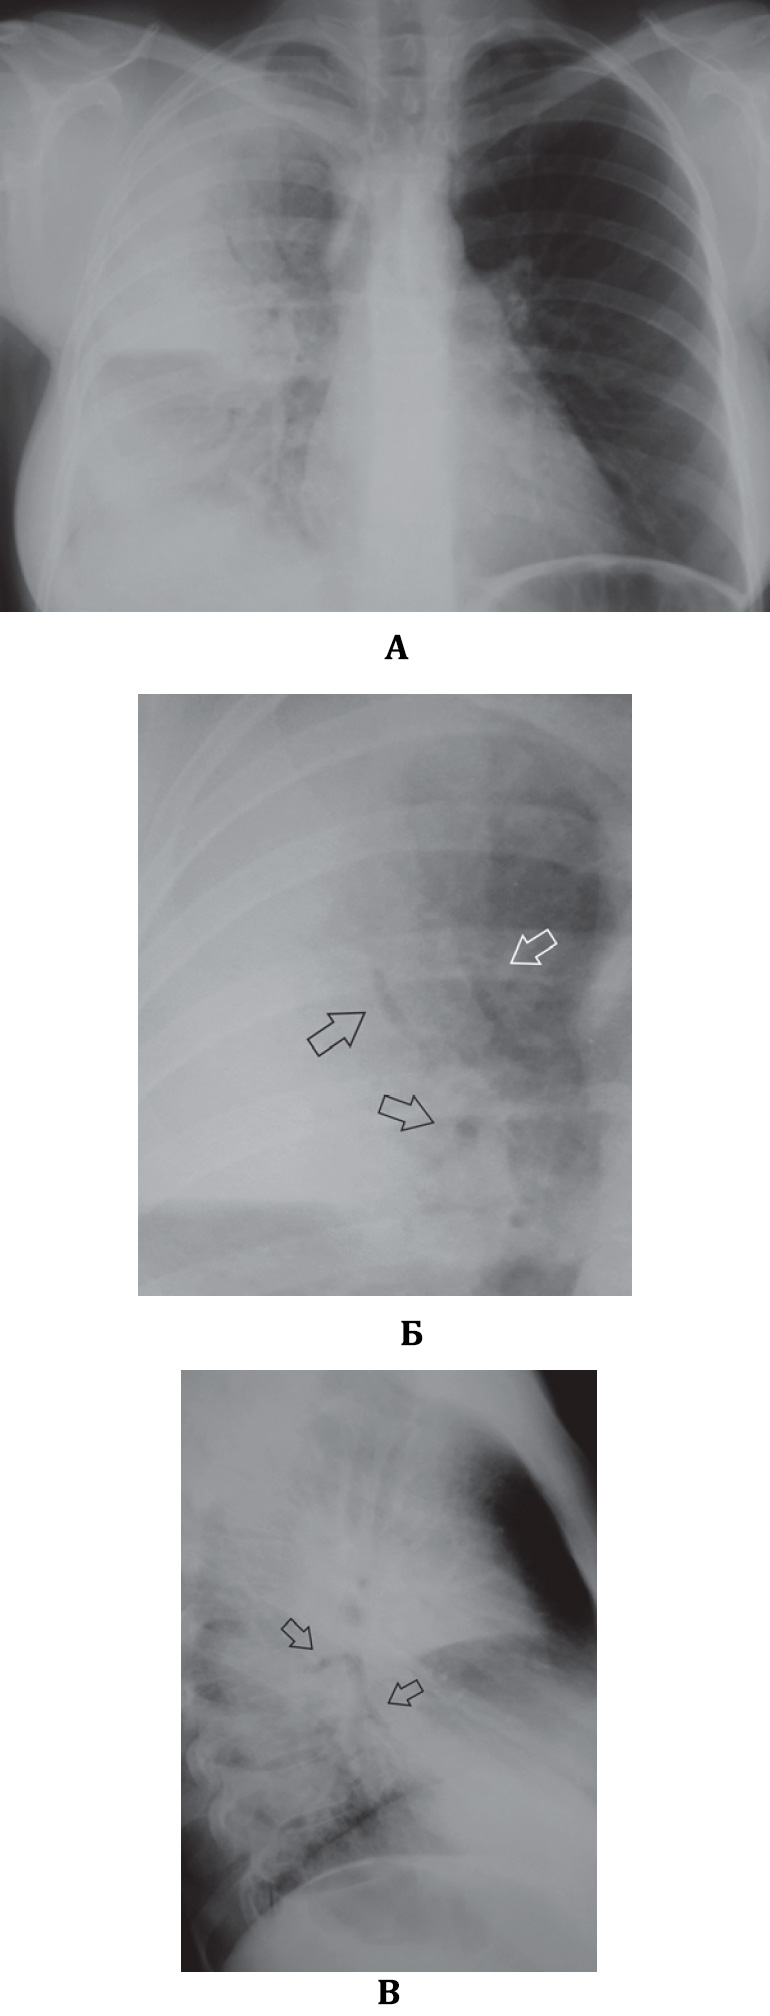

В некоторых случаях на рентгенограмме тяжело определить инфильтрацию S6 нижней доли в прямой проекции, поскольку она наслаивается на тень корня легкого. В этом случае корень легкого определяется как патологически измененный (неструктурным и расширенным) – это может быть причиной неверной диагностики бронхопульмональной лимфоаденопатии. Рентгенография в боковой проекции позволяет избежать эти трудности – не ней хорошо определяется инфильтрация на «верхушке» нижней доли, сзади от корня (рисунок 5).

Рисунок 5. Пневмония S6 (левое легкое). А – рентгенограмма в прямой проекции (слева отмечается инфильтрация в прикорневой зоне, корень легкого выглядит расширенным и неструктурным). Б – рентгенограмма в левой боковой проекции (определяется инфильтрация в «верхушке» нижней доли S6 (см стрелки), которая ограничена спереди междолевой плеврой). В прикорневой зоне нижней доли также определяется небольшой участок неоднородной инфильтрации (см указатель)

В случае обнаружения инфильтрации S6 (особенно в сочетании с инфильтрацией S1 и S2) необходимо обратить внимание на возможный туберкулезный процесс – сопутствующие характерные изменения при туберкулезе: кальцинаты, полости распада, очаги отсева в отдаленных участках пораженного и соседнего легкого, очаговые тени.